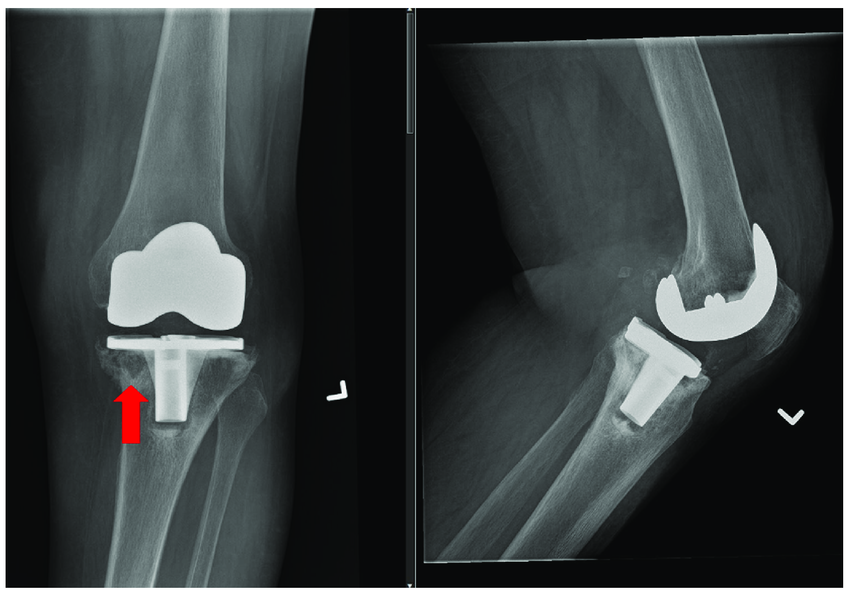

l 股骨远端或胫骨近端有明显的空洞

l 人工关节周围一圈透亮的区域,骨头不见了

l 甚至人工关节直接暴露,周围没有骨头包裹